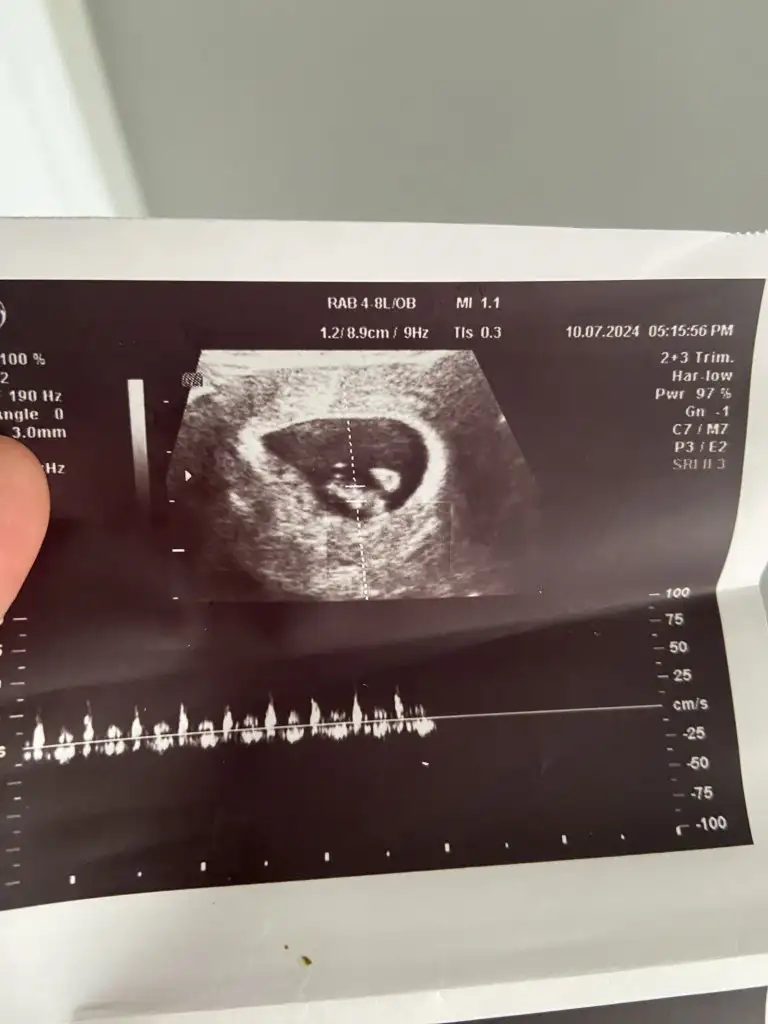

Bu keseyide oğlumunkine benzettim..Sağlıkla gelsinBanada bakabilir misiniz cinsiyeti ne olabilir 10 haftalık Eki Görüntüle 3446085

Bana da bakar mısısnıAlttan bakıldıysa kız ustten bakıldıysa erkek bence

Kaç haftalık? Ve alttan mı ustten mı bakıldı?Cinsiyet tahmini yapar mısınız